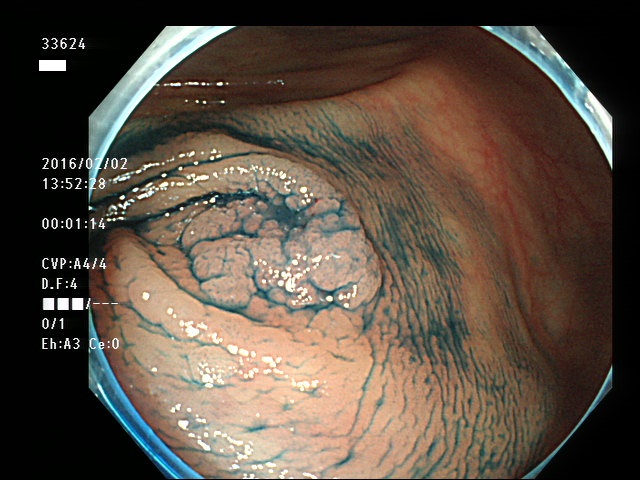

上記100名より抽出した平坦・陥凹型腺腫(=癌化の危険が高いが見落としやすい病変)の内視鏡写真